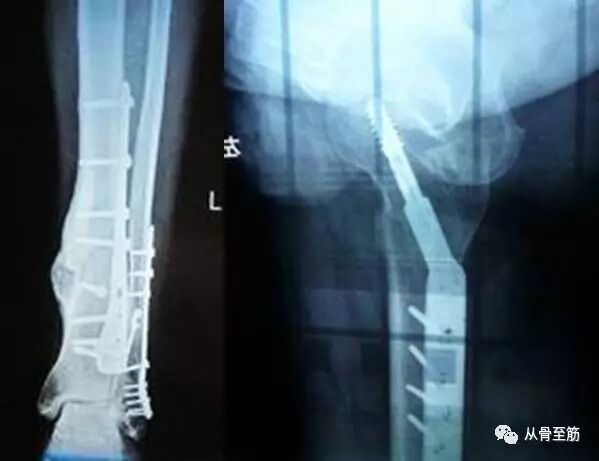

? ? ?第二:内固定取出后,会遗留钉孔,特别是如果取出过程中出现断钉,采用各种办法将断钉取出,钉孔更大,这些钉孔愈合需要时间。在钉孔的局部是力量薄弱区,术后过早负重,可能会因轻微外伤或外力造成骨折。